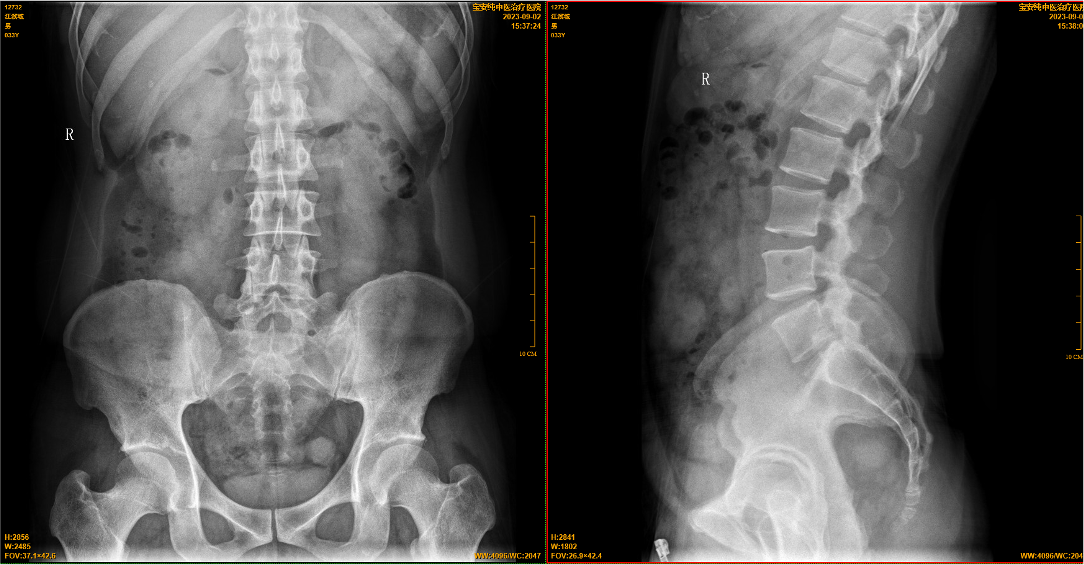

【影像】20230902我院X线见:腰椎轴线轻度侧弯、旋转,生理曲度存在;各腰椎椎体骨质完整,第4~5腰椎椎体前缘上下角轻度骨质增生、变尖,边缘硬化;各腰椎椎间隙未见变窄;第5腰椎左侧横突肥大,并与骶髂骨形成假关节。

患者立位体前屈、左侧屈疼痛加重,前者与臀肌挛缩相关,后者则无法用臀肌挛缩解释。腰椎X线片见第5腰椎左侧横突肥大、并与骶髂骨形成假关节。腰椎左侧屈时,左侧肥大的横突与骶髂骨间挤压力增加而疼痛,痛点与假关节所在相符。故腰椎骶化虽为先天变异,因其引发临床症状,必须下相应的临床诊断。